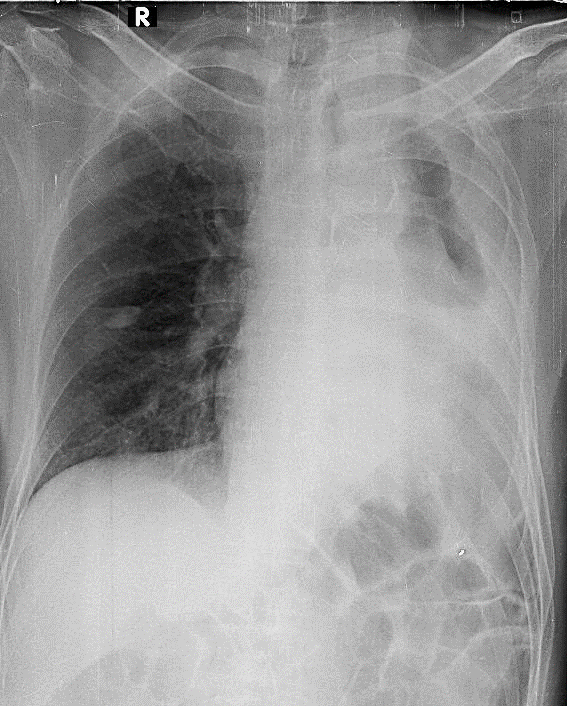

Hãy phân tích tình huống NAM 72 tuổi -CĐ:Viêm phổi cộng đồng, hen phw61 quản, K phế quản trái

1-Tràn dịch màng phổi (T) lượng nhiều 2-Cung động mạch chủ đóng vôi